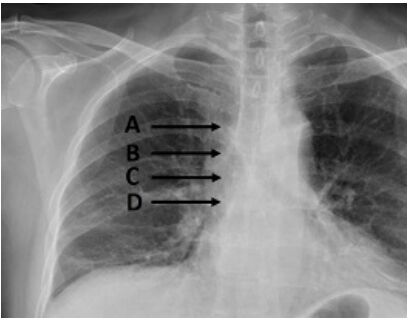

26.中央靜脈導管的尖端應在胸部X光的那個位置較合適?(A)位置A (B)位置B (C)位置C (D)位置D